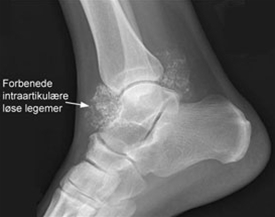

Røntgenbillede vil som regel give diagnosen, idet det viser mange forkalkede mus inde i leddet. Der kan også være slidforandringer. Tidligt i sygdommens forløb kan der dog mangle forkalkninger. MR-skanning er den bedste undersøgelse og kan være nødvendig ved manglende fund ved røntgen eller før en eventuel operation.